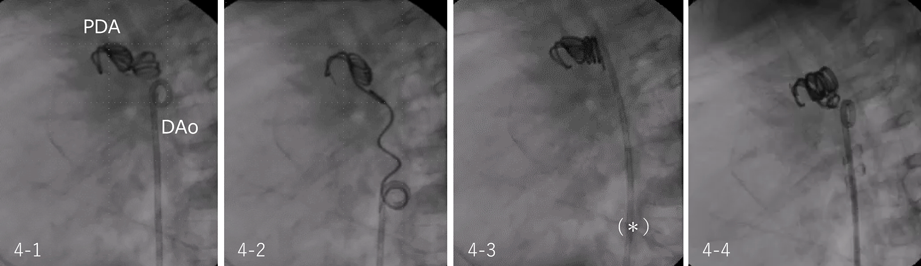

このような場合,立ち上がったコイルを右冠動脈造影用カテーテルやピッグテールカテーテルなどで引き延ばして再離脱すると,コイルループは順行性の巻方に戻り,きれいにまとまった形態で留置される(Fig. 4)(「コイルの特性・特徴」(p. 160)の応用).ただし引っ張り過ぎるとコイルがPDAから抜け出てくるので,動脈管内にあるコイルがしっかり固定されていること,コイルループの位置・形状が変化しないことを確認しながら行う必要がある.

Fig. 4 Coil protrusion in the descending aorta

4-1) According to the mechanism explained in the Fig. 2), the coil loops made bulky lump and protruded in the descending aorta narrow. 4-2) The proximal part of the coil was caught and pulled back by a pigtail catheter until the twist of the coil loops was resolved and finally detached. 4-3) The direction of coil loops aligned with the PDA and the protrusion in the aorta became much better. The coil was pushed into the PDA by inflating the balloon of Berman® catheter (*)[Telefix; Morrisville, NC]. 4-4) PDA was totally occluded with one more coil. DAo, descending aorta; PDA, patent ductus arteriosus